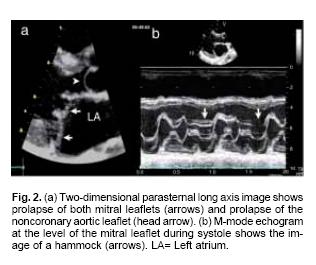

Mitral, tricuspid and aortic valve prolapse was diagnosed by previously established criteria.13,15 Echocardiographic evidence of mitral valve prolapse corresponded to a posterior mitral displacement of at least 2 mm during late systole or a 3 mm displacement throughout systole on M–mode tracings, which was confirmed by billowing of one or both mitral leaflets superior to the plane of the mitral annulus in two–dimensional parasternal long axis views. Pulmonary valve prolapse was defined as the bowing of one or more leaflets into the right ventricular outlet.

Mitral valve prolapse was found in 21 patients (95.5%) of Group I and in 32 (72.7%) of Group II (p = ns, Figs. 2a, b). Tricuspid valve prolapse was detected in 18 (81.8%) patients of Group I and in 26 (59.1%) of those in Group II (p = ns, Fig. 3). Aortic valve prolapse was found in 5 patients (22.7%) of Group I and in 5 (11.4%) of Group II (p = ns, Figs. 4a, b). Furthermore, pulmonary valve prolapse was found in 10 patients (45.5%) of Group I and in 7 (15.9%) of Group II (p <0.03, Table IV, Figs. 5a, b). In contrast, mitral, tricuspid, aortic and pulmonary valve prolapse was not observed in both control groups (p < 0.001) (Fig. 6).